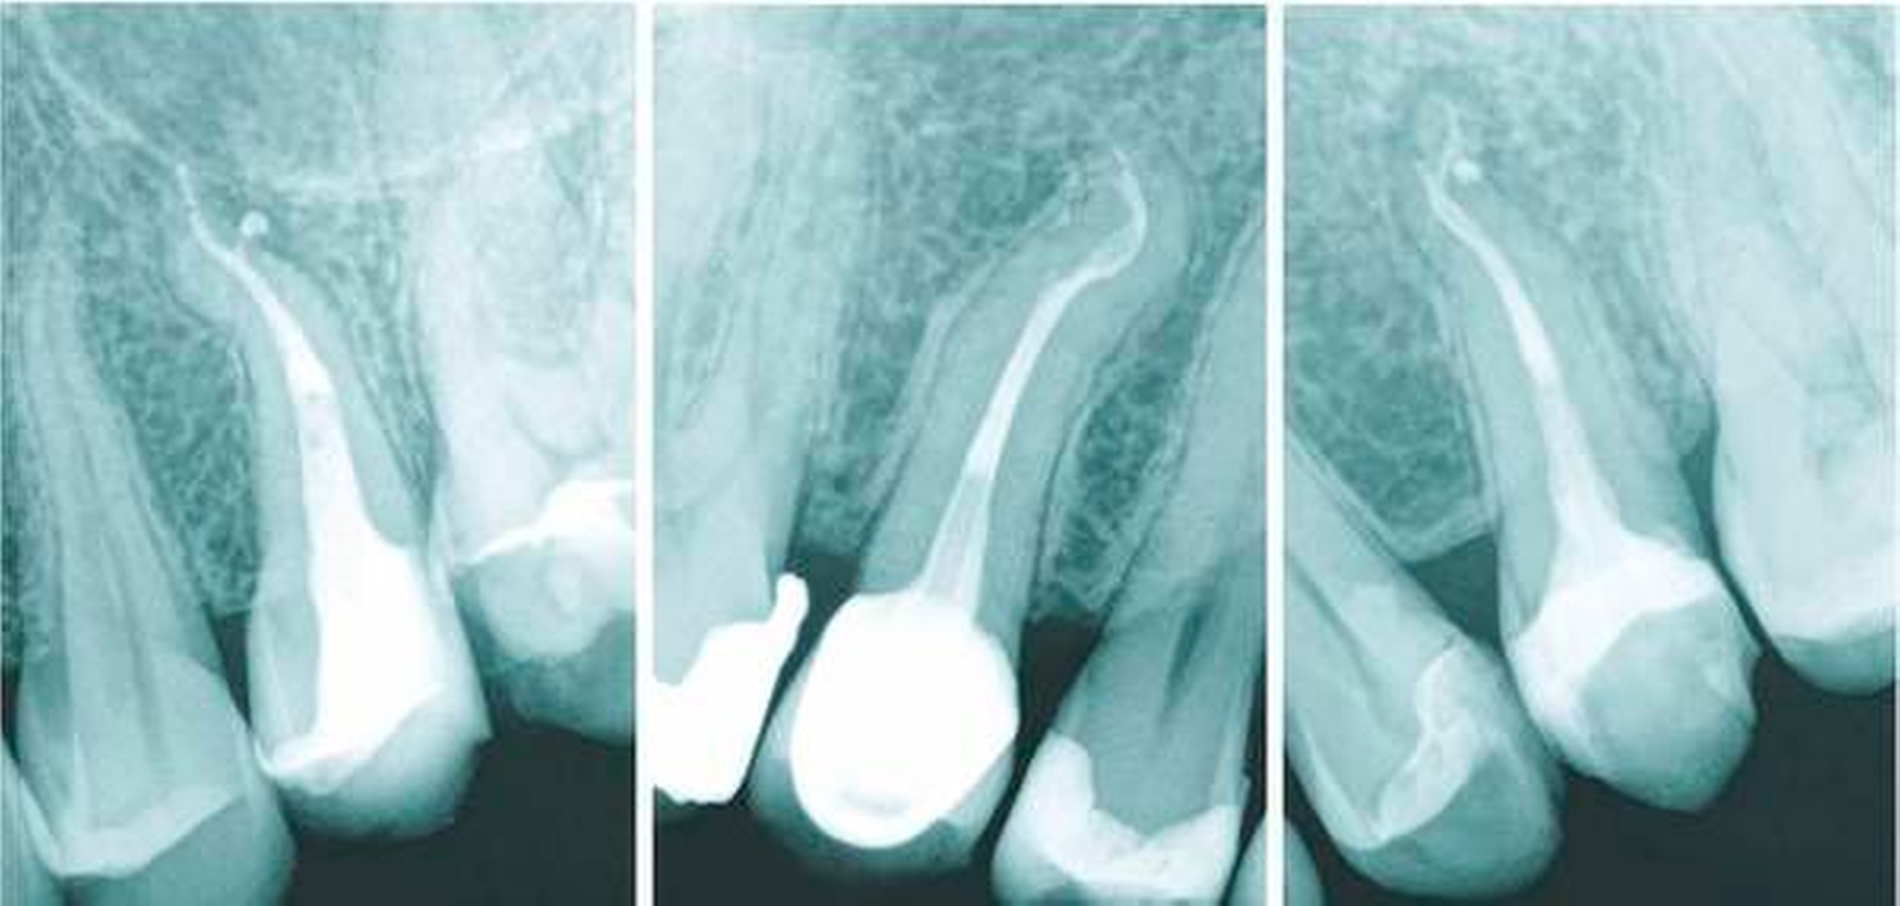

Bestehen großflächige Restaurationen, Kronen oder Brücken, kann das Auffinden der beiden Kanäle sehr schwierig sein. Allgemein konnte gezeigt werden, dass bei restaurierten Zähnen im Vergleich mit einem entsprechenden kontralateralen, restaurationsfreien Zahn eine erhebliche Einengung der Wurzelkanäle stattgefunden hat [Fleig et al., 2017]. Dies kann bei den ohnehin schon eher kleinen Kanälen oberer Prämolaren zu einer erheblichen Einengung und daher zu Schwierigkeiten beim Auffinden dieser Kanäle führen (Abbildung 4).

Drei mögliche Hinweise können bei der Diagnostik eines dreikanaligen Prämolaren hilfreich sein. Der erste Hinweis ist eine nicht klar abzugrenzende Wurzelkontur in der diagnostischen Röntgenaufnahme. Dreikanalige obere Prämolaren zeigen im klassischen Röntgenbild im koronalen bis mittleren Wurzeldrittel eine oft bauchige Struktur. Diese korrespondiert in der Regel mit der Stelle apikal der Aufteilung in zwei bukkale Kanäle (Abbildung 8). Klinisch kann dann in den meisten Fällen bei Sondierung bukkal eine deutliche Einziehung unterhalb der Schmelz-Zement-Grenze mit der Sonde ertastet werden, dies ist der zweite Hinweis (Abbildung 9). Der dritte Hinweis zeigt sich nach Trepanation und Darstellung des Kavumbodens und des vermeintlichen bukkalen Kanaleingangs. Dieser wird häufig nach hinreichender Darstellung in mesiodistaler Richtung oval und gibt dann die Sicht auf die beiden eigentlichen Kanäle frei (Abbildungen 10 und 11).